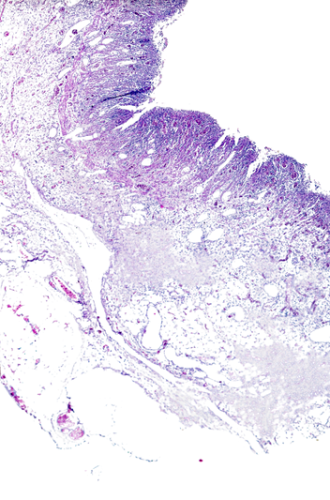

- Dermatopathology Focus: Explore the intricate connections between clinical presentations and pathological findings in dermatology.

- Real-World Cases: Enhance your diagnostic skills with practical, real-world examples.